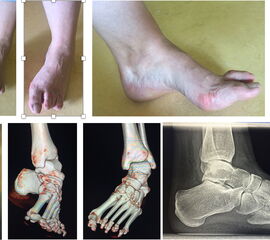

In Deutschland wird bei der Korrektur des Pes equinovarus congenitus seit ca. 20 Jahren das bis dahin verwendete ausgedehnte peritalare release über den Cincinnati approach durch die hocheffiziente Gipstherapie nach Ponseti mit anschließender percutaner Tenotomie ersetzt (Abb. 6). Die Narbe der Tenotomie ist wenige Millimeter klein und später kaum zu sehen.

Abb. 6 a-h: Kongenitaler Klumpfuß (a), Gips-Serie nach der Ponseti-Methode (b), Originalgipsanlagen nach der Ponseti-Methode (c-e), anschließende minimalinvasive Tenotomie (f-g) sowie letzte Gipsanlage in maximaler Abduktion und Dorsdalextension (h).

Knick-Senk-Platt-Fuß Korrektur mit dem Canalis Tarsi Spacer

In der Korrektur des schmerzhaften, aber flexiblen Knick-Senk-Fußes oder Plattfußes ist die Schraubenarthrorise mit einem Sinus tarsi oder besser bezeichnet als Canalis tarsi Spacer und alternativ mit einer Calcaneus-Stopp-Schraube seit vielen Jahren ein etabliertes Verfahren und führt zu einer kompletten Korrektur von flexiblen Knick- und Plattfuß-Fehlstellungen (Abb. 7). Die nötige Schnittlänge über dem Sinus tarsi beträgt für beide Verfahren 1 cm.